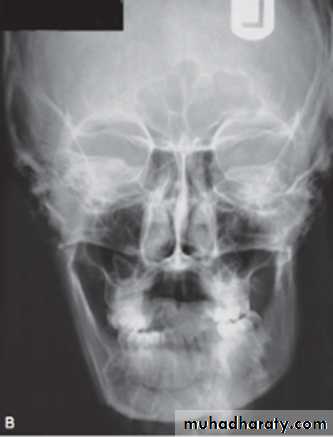

1- Condylar Hyperplasia:- Enlargement and deformity of the condylar head.

- Secondary effect on the mandibular fossa as it remodels to accommodate the abnormal condyle.

Etiology: Trauma, infection, hereditary

More common in males.

Self limiting.

Progresses slowly or rapidly.

Mandibular asymmetry.

Chin deviated to the unaffected side.

Radiographic Features:

• May appear normal but symmetrically enlarged or it may be altered in shape (e.g., conical, spherical, elongated, lobulated)or irregular in outline.

• May be more radiopaque due to additional bone present.

• Condylar head & neck may be elongated with a compensating

forward bend, forming an inverted L.

• Glenoid fossa may also be enlarged.

• Ramus and mandibular body on the affected side also may be enlarged, resulting in a characteristic depression of the inferior mandibular border, increased vertical dimension of ramus and may be thicker in the anteroposterior dimension.

Treatment:

Orthodontics combined with orthognathic surgery.